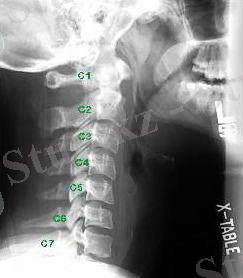

Рис. 2. Омыртқаның мойын бөлімінің Рентгеногграммасы

а- схема, б - хэнгман сынығы ( «асылған »), в - С2 омыртқа тісінің сынығы

Радиологиялық зерттеулер. Тексеруді көрсеткіш екі проекциялы ретгенннен бастайды, алдыңғы артқы және бүйір, рентгенограмманың ортасында клинасмен анықталған зақымданған ошақ орналасады. Алдынғы артқы проекцияда көлденең өсінділер зақымдануы, омыртқалардың бүйірлык шығулары, ал қалған сынықтар бүйір проекцияда жақсы көрінеді. Әдеттегі сынықтардардың орнын білу кезінде рентгенологиялық тексеру барысында барлық кеуде бел ауысуын (бел омыртқаларының сынығына күдіктенгенде ) және мойын- кеуде ауысуында төменгі мойын омыртқаларының сынығын анықтағанда, науқас қолы төменге қарай, иық және иықүсті буының төмен түсіру арқылы рентген суретін жасаймыз. Рентгенограмманы бағалаған соң, керек жағдайда томограммыа, қиғаш проекциялы рентгенограмма, жасауға болады, Омыртқаның шығуы болатын болса, жоғары орналасқан омыртқа шыққан деп есептеледі. (рис. 5 а, б)

Омыртқа денесінің сынығының рентгендік көрінісі ретінде бүйір проекциядағы сына тәрізді деформация болып табылады. (рис. 5, в) .